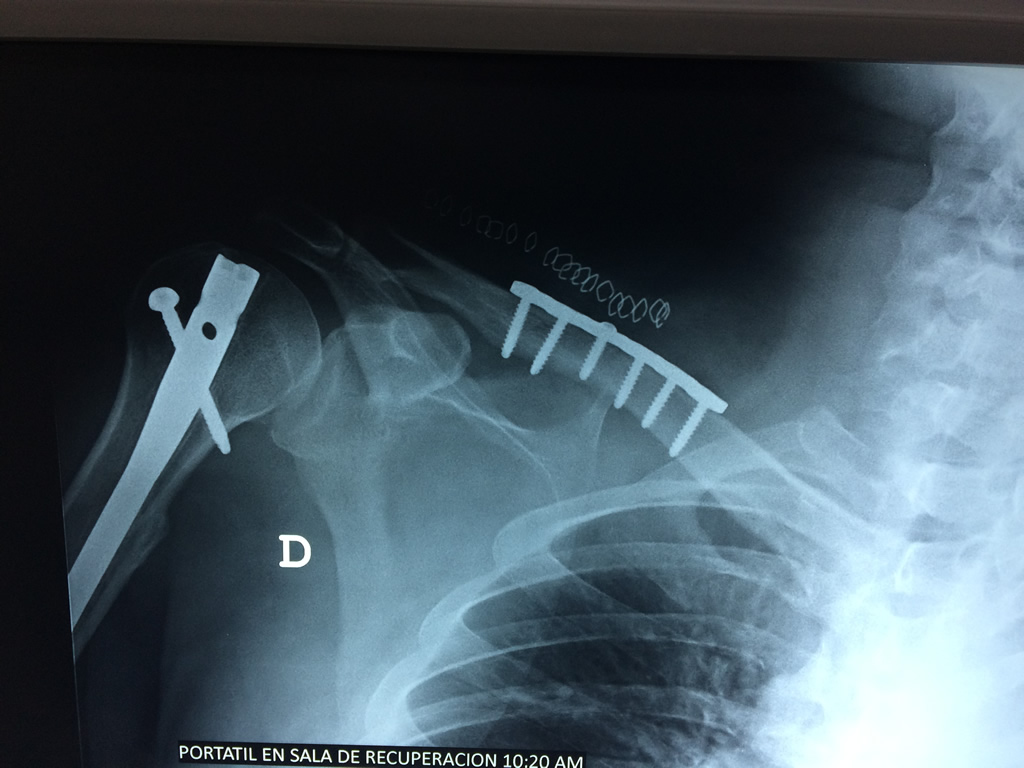

Cirugía de Fémur - Clavícula